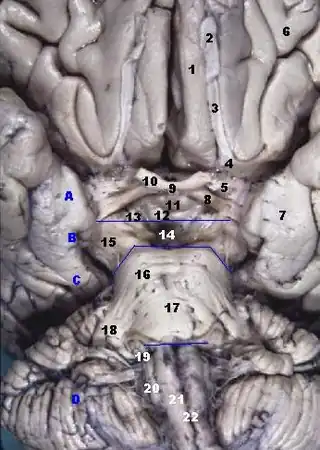

Base del encéfalo. El giro recto está señalado con el número 1. | ||

Animación la circunvolución recta se muestra en rojo. Superficie basal del del cerebro. La circunvolución recta se muestra en rojo.

Superficie basal del del cerebro. La circunvolución recta se muestra en rojo. Circunvolución recta vista anteriormente en el centro.

Circunvolución recta vista anteriormente en el centro.